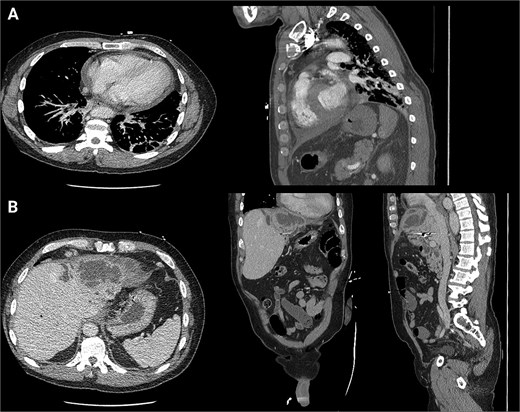

He was seen in the clinic 6 days later. At that time, he reported worsening abdominal pain and orthopnea. Repeat imaging showed that the hepatic abscess was stable in size, but the pericardial effusion had worsened and that the hepatic abscess had broken through the right hemidiaphragm (Fig. 4). Given his multiple instances of failed management, HPB Surgery elected to perform diagnostic laparoscopy. A TTE was performed, which showed a loculated pericardial effusion. Cardiothoracic Surgery (CTS) was consulted to see if drainage was indicated. They deemed that a pericardial window was needed, but it would depend on the outcome of the hepatic abscess drainage.

Second readmission imaging—CT of the chest in the axial, sagittal, and coronal views. These demonstrate that the abscess has eroded through the diaphragm and now abuts the pericardium. Additionally, it shows a worsening of the pericardial effusion, concerning for abscess communication.